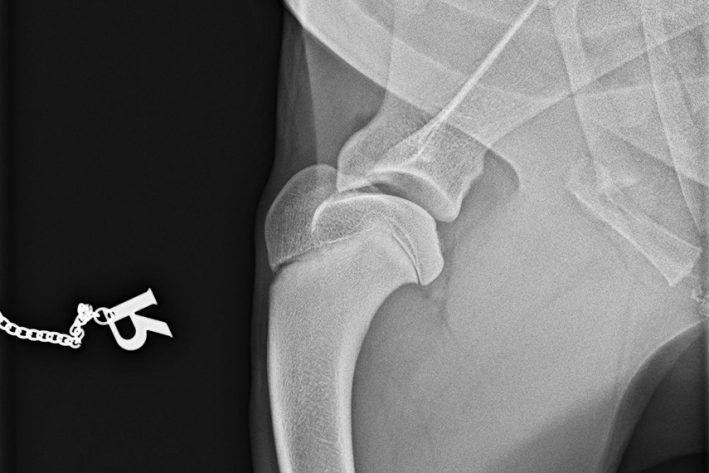

Die Diagnosestellung erfolgt in der Regel während einer orthopädischen Untersuchung durch Ihren Tierarzt in Kombination mit Röntgenbildern und/oder CT.

Röntgen OCD